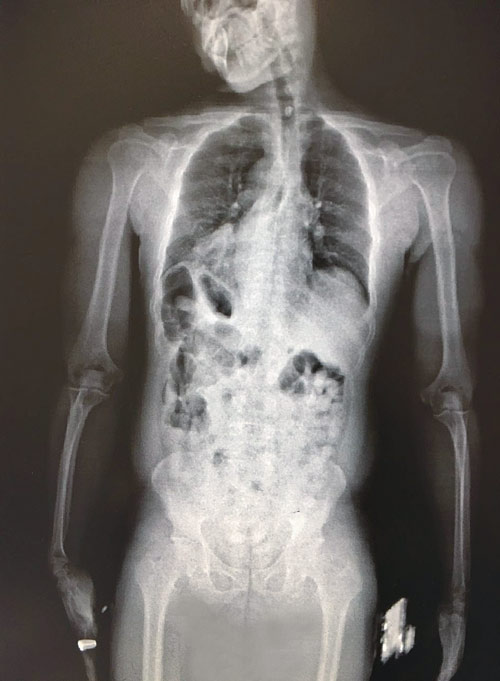

وأكد فيصل الدباغ مدير عام جمرك مطار الأمير محمد بن عبدالعزيز إنه عند إنهاء الإجراءات الجمركية لركاب إحدى الرحلات القادمة اشتبه المراقب الجمركي بأحد الركاب وعلى الفور تم التأكد من حالة الاشتباه وذلك بإحالة الراكب لجهاز فحص الأحشاء بالأشعة، وبالفعل عُثر بداخل أحشاء هذا الراكب على (83) كبسولة صغيرة الحجم تحتوي بداخلها على تلك الكمية من مادة «الكوكائين». وأضاف الدباغ أنه جرى بعد ذلك اتخاذ الإجراءات اللازمة حيال ذلك، مؤكداً في الوقت نفسه أن الجمارك السعودية تبذل أقصى جهودها في سبيل منع كل ما من شأنه الإضرار بالوطن والمواطن، ومبيناً أن الجمارك سعت من أجل ذلك إلى توفير كافة الإمكانات من الكوادر البشرية المؤهلة والتقنية الحديثة حيث ساهم ذلك في تحقيق الجمارك للعديد من النجاحات في مجال مكافحة التهريب بكافة أنواعه.